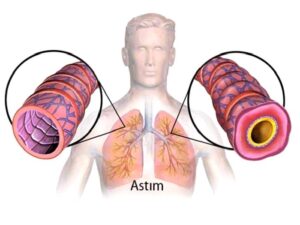

Astım hastaları

Kronik akciğer hastaları (KOAH, Sarkoidoz vb.)